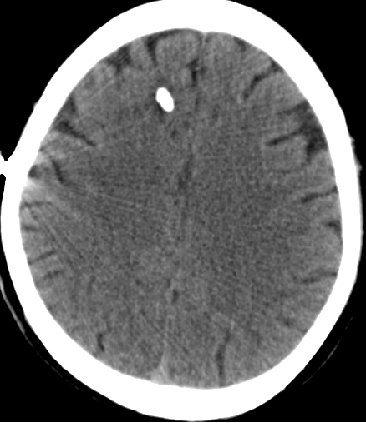

2014-10-17 CT

仍时有前额部疼痛,程度轻,调压190—200